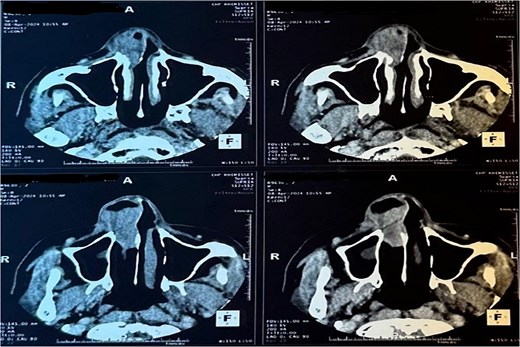

A CT scan revealed a mass centered on the right inferior turbinate, with no bony involvement but a polypoid filling of the right maxillary sinus, raising concern for malignancy (Figs 2 and 3).

Tomography image of the paranasal sinuses in axial slice with parenchymal window revealing a tumoral-like mass in the right nasal cavity, centered on the right inferior turbinate.